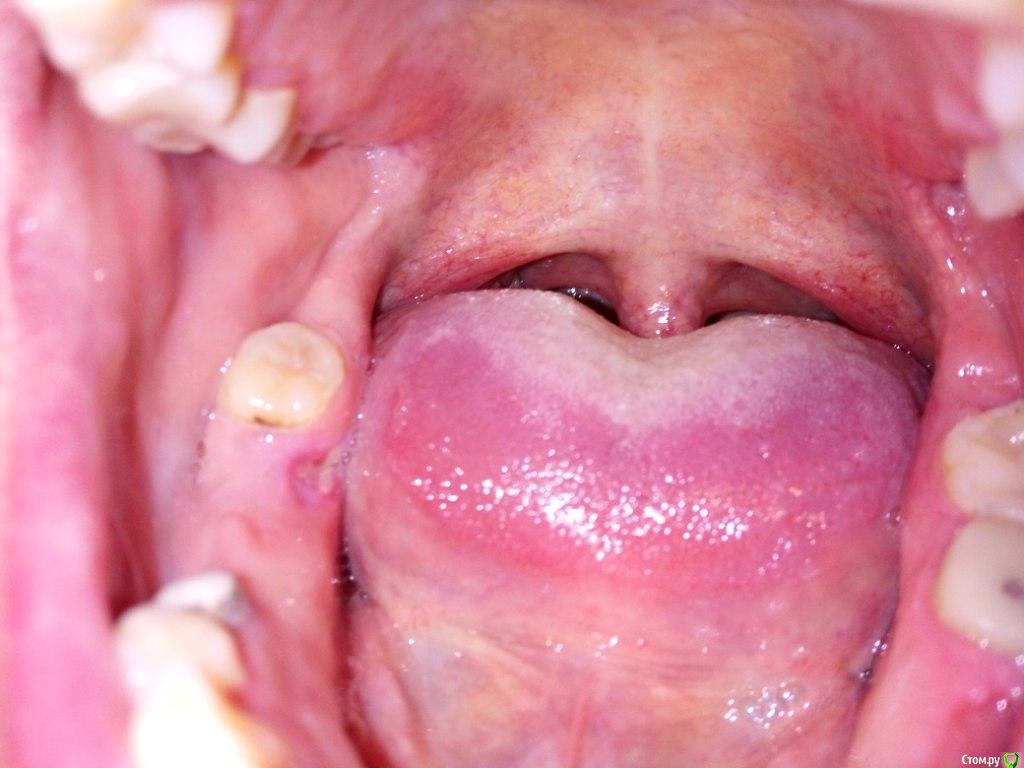

Некий Опубликовано 6 марта, 2017 Поделиться Опубликовано 6 марта, 2017 (изменено) Добрый день! 30.11.2016 - пришлось удалить 47 зуб на фоне воспаления.Удаление быстрое, но производилось не вверх, т.к. штифтованная конструкция развалилась, а в бок.Дня через 4 вышел синяк и немного побаливало.Доктор сказал, что заживление идет штатно.Но так и не заживало окончательно до 06.01.17.В это посещение был удален секвестр костный.После этого в течении недели все заросло.Но оказалось не совсем, т.к. 14.02.17 обнаружил, что острый край (вероятно, сломанной лунки) прорвал десну.С тех пор уже трижды проводили кюретаж поврежденного участка с шлифованием кости. Первый раз ничего не назначая, второй - метрогил дента, третий- солкосерил.Прошла неделя с последнего лечения. Результат не радует Что предпринять в данной ситуации? Заранее спасибо. Изменено 6 марта, 2017 пользователем Некий Ссылка на комментарий